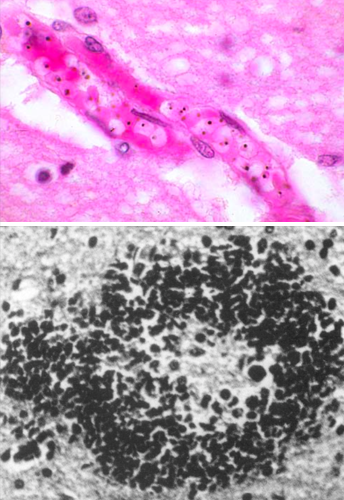

A 25 year old male medical student who recently returned from Mexico with his wife after spending spring break in Cancun, complained of painful defecation. His stools have changed color and have white purulent areas and occasionally are blood tinged. His bowels are active and his abdomen is tender to palpation, no guarding is present. Parasites are found in his bowel as shown below. What is likely causing his condition?

Entamoeba histolytica has cysts that resist gastric acid. They then wedge into the GI mucosa and cause ulcerations. Note the red blood cells phagocytosed by the amoeba.

What parasite causes the lesions shown below in the GI tract? What other complications can arise form this infection?

Note the “flask-shaped” ulcer, typical of entamoeba histolytica. It gets to the liver via the splanchnic vessels and causes abscesses. Liver abscesses can also break through the diaphragm and enter the pleural space.